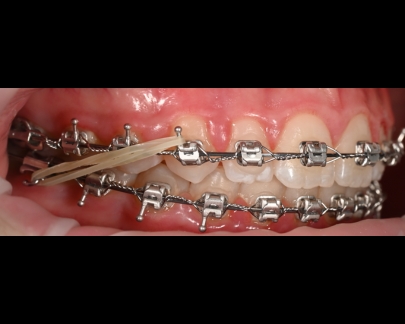

Sunt benzi elastice mici, din latex, folosite pentru corectarea mușcăturii și intercuspidarea dinților.

Elasticele se atașează de brackeții dinților superiori, respectiv inferiori și vin în diferite dimensiuni și grade de forță.

Elasticele ortodontice corectează raportul dintre maxilar și mandibulă (mușcătura). Sunt purtate conform indicațiilor medicului și sunt esențiale în multe tratamente pentru alinierea corectă a arcadelor.